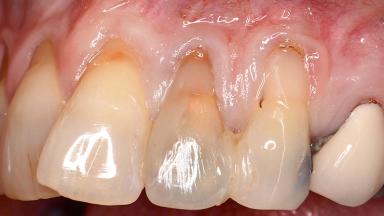

Variations in soft-tissue volume, evidenced either by an overabundance (Evian and coworkers 1993; Levine and McGuire1997; Dolt and Robbins 1997) or by a deficiency of soft or hard tissue can complicate implant-supported rehabilitations in the esthetic zone (Lorenzana 2008; Lorenzana and coworkers 2009). The present case illustrates the replacement of a failing upper left lateral incisor complicated by generalized severe gingival recession in the esthetic zone.